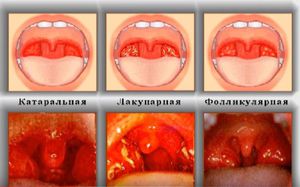

На изображении заметно яркое покраснение слизистой оболочки.

При осмотре горла врач заметит увеличенные небные миндалины, отек и покраснение дужек слизистой глотки. Эти симптомы ограничены областью небных дужек. При распространении воспаления на более глубокие ткани начинается фарингит, что представляет собой отдельное заболевание, требующее отдельного лечения. Обычно это происходит с обеих сторон. Лимфоузлы подчелюстной области становятся болезненными при ощупывании и увеличиваются в размерах. Появляется острая боль при глотании.

При проверке горла обнаруживаются: увеличение красноты и отечность слизистой оболочки глотки, а также увеличение размеров миндалин неба. При этом процесс двусторонний и не распространяется дальше слизистой оболочки.

Во время визуального осмотра врач заметит увеличение небных миндалин, красноту слизистой глотки и отек. Внешний вид этих симптомов можно изучить на изображениях в медицинских справочниках.

При обращении к медицинским справочникам можно обнаружить изображение воспаленной глотки и изучить основные признаки заболевания. Это поможет своевременно распознать начало заболевания.